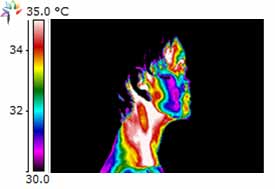

Dental Case Study 2

Patient exhibits Necrotic Molar in the lower left jaw.